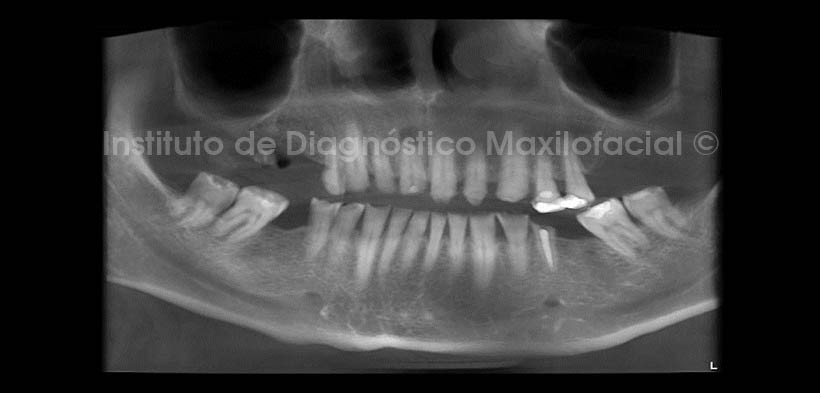

En la evaluación con tomografía volumétrica, en la reconstrucción panorámica (Fig.2) se observa la perdida de estructura dentaria mencionada, así mismo nótese la lesión apical en la pieza 1.1, la misma que en la radiografía panorámica se mostraba discretamente.